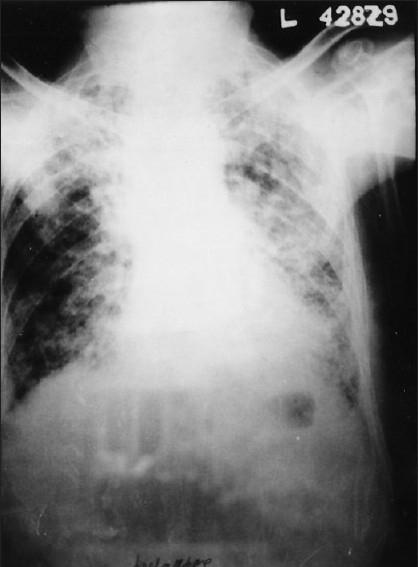

Diphenylhydantoin (phenytoin)-induced chronic pulmonary disease.

Drug-induced respiratory diseases are difficult to diagnose and therefore usually not identified, probably underestimated and under-reported. We report a case of diphenylhydantoin/phenytoin-induced chronic pulmonary disease in a 62-year-old male patient presenting with progressive dyspnea, eosinophilia, and pulmonary abnormalities. The importance of drug history in clinical history-taking and early diagnosis of drug-induced respiratory diseases is emphasized so as to prevent permanent pulmonary damage.

药物性呼吸道疾病难以诊断,因此通常未被识别,可能被低估且报告不足。我们报告一例62岁男性患者,因服用二苯乙内酰脲/苯妥英钠诱发慢性肺部疾病,该患者表现为进行性呼吸困难、嗜酸性粒细胞增多和肺部异常。强调了用药史在临床问诊及药物性呼吸道疾病早期诊断中的重要性,以预防永久性肺损伤。